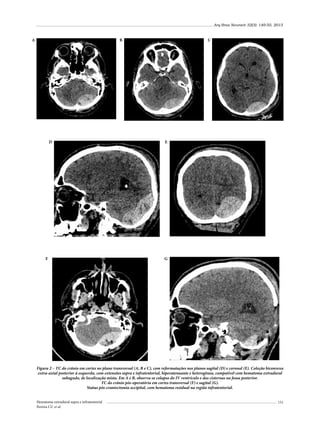

over was the main cause of these lesions (single nerve and multiple nerves). Extradural hematomas were

the most frequent intracranial lesions and the absence of cranial fractures were dominant. Conclusion:

Traumatic olfactory neuropathy occurs must be searched on the patient admission (whenever it is

possible), especially in those cases in that frontal or occipital fractures are present.

KEYWORDS

Cranial nerve injuries, craniocerebral trauma, olfactory nerve.

Introdução

A lesão isolada ou combinada de nervos cranianos é achado relativamente frequente quando decorrente de traumatismo cranioencefálico (TCE).

De acordo com Patel et al.,1 em 12,6% dos casos

de TCE ocorreram lesões dos diferentes nervos

cranianos, com nítido predomínio de acometimento no gênero masculino e traumas resultantes de

mecanismos de baixa energia cinética.

São lesões frequentemente despercebidas nos

exames neurológicos de entrada em prontos-

1	 Médico-assistente da disciplina de Neurocirurgia da Irmandade Santa Casa de Misericórdia de São Paulo (ISCMSP), São Paulo, SP, Brasil.

2	 Professor adjunto e chefe da disciplina de Neurocirurgia da ISCMSP, São Paulo, SP, Brasil.

Arq Bras Neurocir 32(3): 170-80, 2013

-socorros e muitas vezes somente perceptíveis ou

evidentes tardiamente durante a evolução do processo traumático.2 Pacientes comatosos podem ter

lesões traumáticas de nervos cranianos e, por causa

do comprometimento do nível de consciência,

essas lesões podem não ser detectadas. Exceções

se fazem aos nervos oculomotor (III), abducente

(VI) e facial (VII), que evidenciam lesão sem a